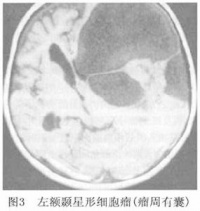

4.MRI检查 星形细胞瘤在MRI上T1W呈低信号 T2W呈高信号。MRI可清楚显示肿瘤浸润脑组织的程度。增强后星形细胞瘤一般不强化, 少数肿瘤有周边斑点状轻度强化影。良性星形细胞瘤由于肿瘤的生长,使肿瘤内外水分增多,造成T1和T2延长 表现T1加权像呈低信号,T2加权像呈高信号(图3),信号强度均匀,瘤周水肿轻微,注射Gd-DTPA增强不明显。随着肿瘤的生长,瘤内发生囊变使得MRI不均匀,瘤体和周围水肿在T1加权像上不如T2加权像上容易区分,肿瘤可有轻度的增强, 恶性星形细胞瘤在T1加权相上呈混杂信号 以低信号为主,间以更低信号或高信号,体现了肿瘤内坏死或出血。